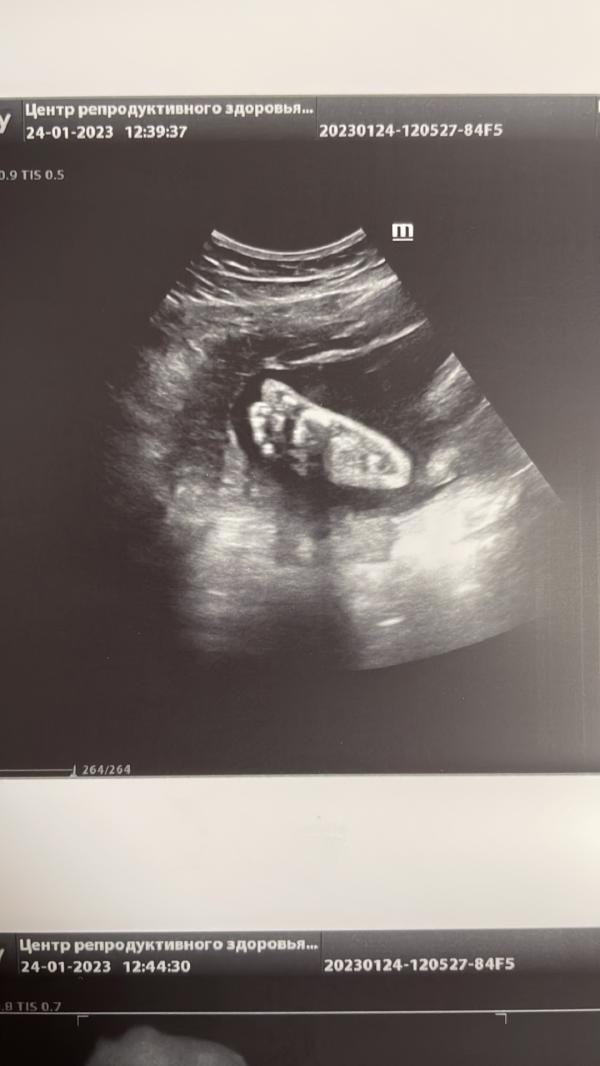

Сходила на УЗИ и вот такую ножку смогли запечатлеть на память 🦶

Гляди какие ножки красивые ,как у модели 🤪👍🔥 будет высокий 100% и красавец 😍🌺 тьфу тьфу тьфу

Ой ,потом эту ножку зацелуете ...это самое сладкое у малышей ,розовые пяточки 😍🙏

Вообще 🥰так неожиданно получилось такое фото, я прям думаю в рамочку поставить на память))